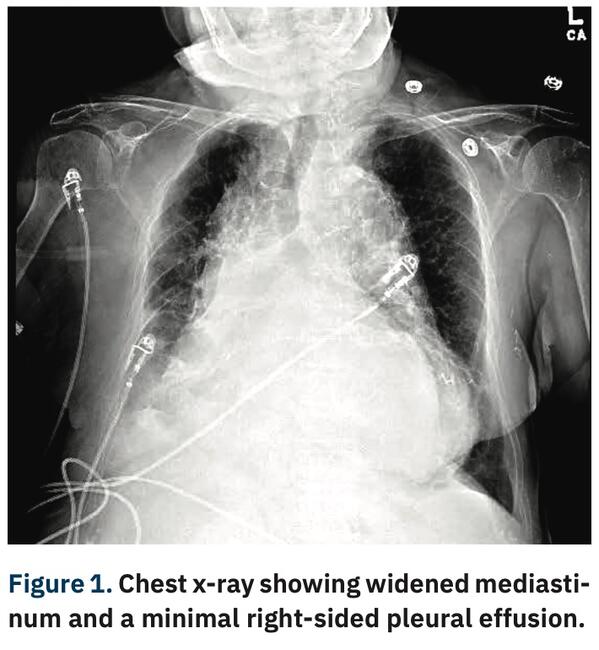

Unusual Presentation of Descending Thoracic Aortic Aneurysm

Thoracoabdominal aortic aneurysms (TAAA) result from continuous dilation of the descending thoracic aorta extending into the abdominal aorta. Degradation of the structural proteins that form the medial layer of the aorta, like collagen and elastin, causes degeneration and weakening of the aortic wall.1 Symptoms often occur after the aneurysmal diameter is greater than 5 cm; the most common initial symptoms may be vague pain in the back, chest, flank, or abdomen. It may be confused with angina, aortic dissection, or degenerative disease of the spine. Hoarseness of voice due to stretching of the left recurrent laryngeal nerve can occur. Occasionally, TAAA presents as a pulsatile abdominal mass.2 TAAAs are asymptomatic in 95% of cases, meaning most TAAAs remain undetected unless incidentally discovered.3 Herein, we describe the case of a patient who was initially treated for fluid overload as an outpatient, but a TAAA was ultimately discovered and she was treated via an endovascular approach.